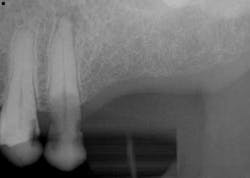

Surgery commenced. Implants on the lower arch were placed first (figures 7 and 8) and then we switched to the maxillary. The teeth were removed (figures 9 and 10) and the ridge was evened out (figures 11-13). The implants were aligned with the denture (figure 14) and then placed accordingly (figures 15-17). Healing caps were put on, and we were ready to start the restorative phase (figures 18-19).